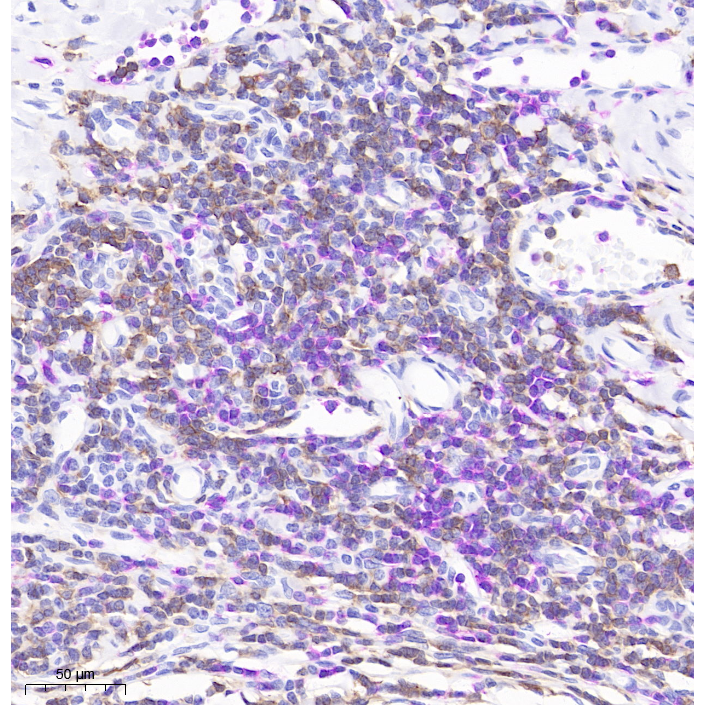

Human tonsil histochemical double staining: red chromogen-CD3 (pink), DAB-CD20 (brown)

Picture

Human tonsil histochemical double staining: red chromogen-CD3 (pink), DAB-CD20 (brown)